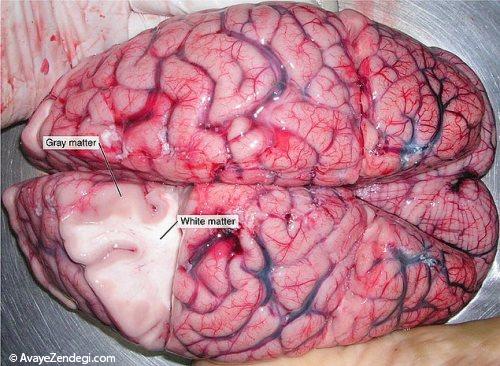

5- موضوعات بحث برانگیز مربوط به جنسیت در مغز؛ با توجه به بررسی های انجام شده در سال 2014، مقدار بیشتری از ماده خاکستری در مغز زنان موجود است.

6- ماده خاکستری مربوط به مهارت های زبان می شود و بسیار پیشرفته است.

7- با توجه به مطالعات انجام شده، اگر شما به طور منظم ورزش کنید، می توانید مقدار ماده خاکستری واقع در هیپوکامپ را افزایش دهد.

8- اطلاعاتی جالب؛ ماده خاکستری که 40٪ مغز را تشکیل می دهد، تنها پس از مرگ، به رنگ خاکستری در می آید.

9- مغز انسان زنده به رنگ صورتی می باشد و دانشمندان معتقدند مغز انسان دارای قوام پنیر تافو است.

10- مقدار ماده سفید در مغز مردان بیشتر است و تصور می شود این ماده، مایع مغزی نخاعی است.

11- 60 درصد از ماده سفید مغز، از میلین ها تشکیل شده که سرعت انتقال پیام الکتریکی را با کمک این ماده سفید، افزایش می دهد.